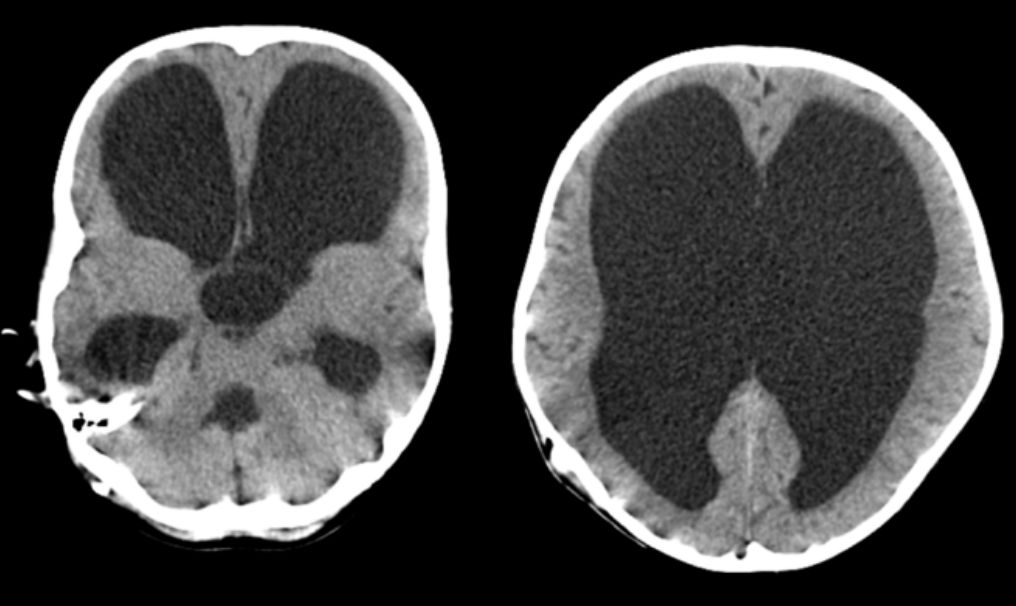

与术前对比,头围缩小致57cm,颅高降低较明显,约有7cm,总颅腔体积缩小24.7%(图7)。

![]()

图7. 术前术后外观及头围比较(左:术前,右:术后)

缩颅术后7年随访复查,显示外观基本正常,颅骨三维重建愈合良好(图8)。

图8. 术后7年随访,外观基本正常,头颅三维CT显示颅骨愈合良好。

目前术后随诊中,侧脑室腹腔分流管压力1.5,头围58.5cm,正常上学。